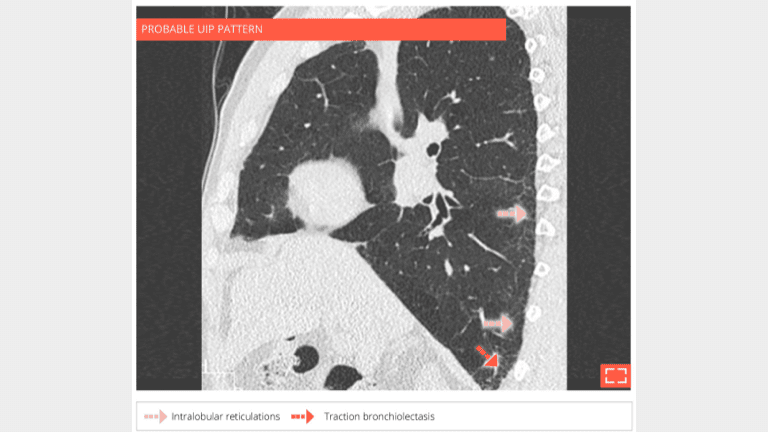

4. Intralobular reticulations

• Isolated and subtle subpleural intralobular reticulations.

• No ground-glass opacity or honeycombing or traction bronchectosis.

5. Intralobular reticulations

• Isolated and subtle intralobular reticulations, with traction bronchiolectasis.

• No ground-glass opacity or honeycombing.